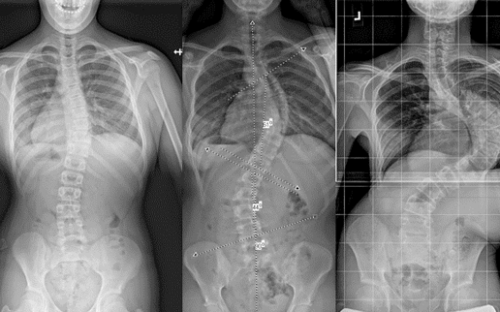

تقليديًا، كان الأطباء يقيّمون الجنف باستخدام صورة أشعة أمامية تقيس زاوية كوب فقط.

ولكن في الواقع، الجنف ليس انحناءً جانبيًا فقط، بل هو تشوه ثلاثي الأبعاد يشمل:

الانحناء الجانبي (المستوى الأمامي)

الدوران الفقري (المستوى المحوري)

التغيرات في تقوس الظهر الطبيعي (المستوى السهمي)

لذلك، أصبح من الضروري دراسة العمود الفقري والقفص الصدري في الثلاثة مستويات معًا لفهم مدى استجابة الطفل للحزام.

1. درجة التصحيح داخل الحزام (In-brace Correction)

أحد أقوى المؤشرات على نجاح العلاج هو مدى تحسن زاوية كوب أثناء ارتداء الحزام مباشرة.

فكلما كانت زاوية الانحناء داخل الحزام أصغر، زادت فرصة السيطرة على الجنف على المدى الطويل.

إذا لاحظ الطبيب تحسنًا واضحًا في الأشعة داخل الحزام، فذلك مؤشر إيجابي قوي للأهل.